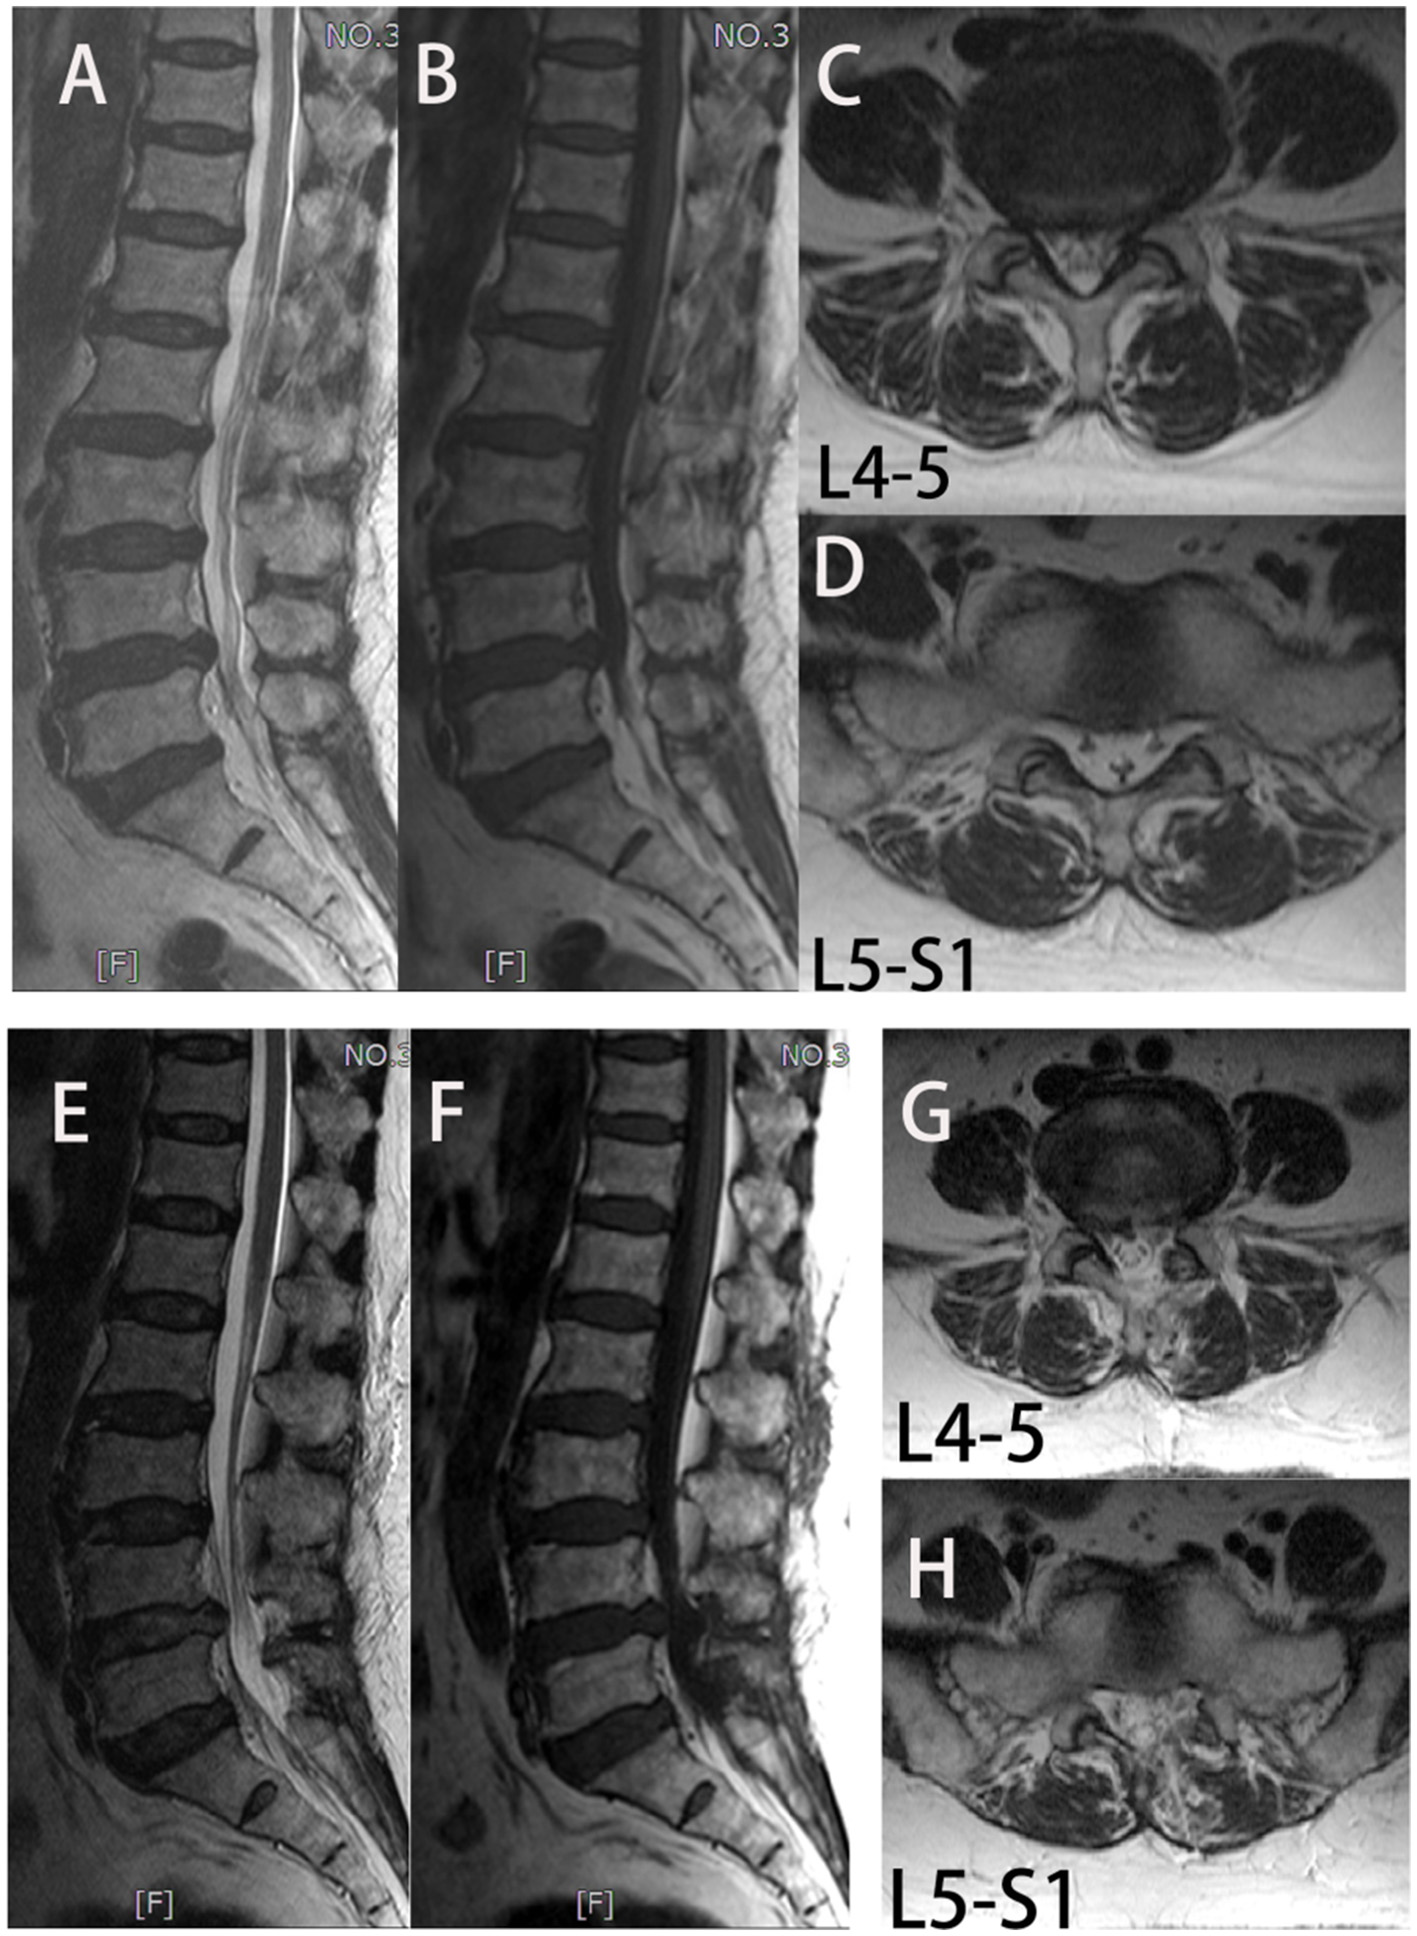

The NRS and ODI scores of the two groups at 1 week and 1 year after surgery were significantly improved compared with those before surgery (p < 0.05). However, the NRS and ODI scores of the UBE-ULBD group were significantly higher than those of the OLD group on the 7th day after the operation (NRS: 3.00 ± 0.65 vs. 4.00 ± 0.84; ODI: 37.27 ± 2.25 vs. 39.44 ± 2.55, p < 0.01, Table 4). The RMDQ and SF-36 (physical and mental component) scores of the two groups 1 year after the operation were significantly improved compared with those before the operation (p < 0.05). The patients presented with clearly reduced pain-associated disability. There was no significant difference in the RMDQ and SF-36 (physical and mental component) scores between the two groups at 1-year follow-up. Due to the clinical benefits, patient satisfaction in both groups was high. In the 1-year follow-up, 80% of patients in the UBE-ULBD group scored Odom's criteria with “good” or “excellent,” as 77.8% of patients in the OLD group did (Table 4). Among the four patients with adverse symptoms, one underwent lumbar fusion surgery 3 months after surgery, and three received conservative treatment for symptom control. Typical case is shown in Figure 2.

Figure 2

In group UBE-ULBD, a 56-year-old woman suffers from low lumbar pain accompanied by lower limb pain and numbness for more than 1 year, diagnosed to be L4-5 and L5-S1 LEL. (A–D) Preoperative MRI examinations showed severe LEL at L4-5 and L5-S1 levels. The patient received UBE-ULBD, and symptoms were significantly relieved after the surgery. (F–H) Postoperative MRI indicated completed decompression was achieved at L4-5 and L5-S1.